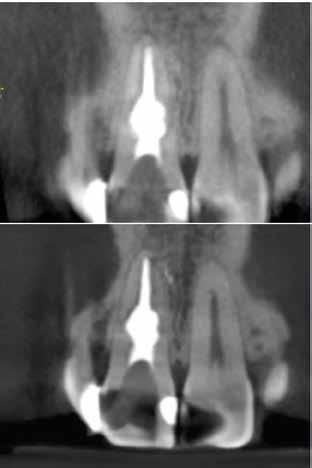

4. a–b. ábra: A reszorbciós üreg Biodentine-nel való feltöltése. Intraoperatív (a) és radiológiai felvétel (b). – 5. ábra: Az öt hónappal később látható állapot. Nem észlelhetők gyulladás fennállására utaló jelek.

A kezelés befejezését követően 30 hónappal készített CBCT-felvételen a gyógyulás jelei észlelhetők.

A gyökértömés elkészítése során meleg vertikális kompakciós technikát alkalmaztunk, sealerként pedig CeraSeal-t (Meta Biomed; 3. ábra) használtunk. A reszorbciós üreget Biodentine-nel (Septodont; 4. a–b ábra) töltöttük fel. A reszorbcióval érintett területtől koronális irányba elhelyezkedő csatornaszakaszt pedig tisztán meleg guttaperchával kezeltük. Ezt követően a lebenyszéleket visszafektettük, és varratok behelyezésével eredeti pozíciójuknak megfelelően rögzítettük. A koronai részt kompozit tömőanyag segítségével állítottuk helyre. Kontrollvizsgálatra 5, illetve 30 hónappal később került sor (5. ábra). A csontos telődés jelei már 5 hónap után észlelhetők voltak (6. a–c ábra). A 30 hónappal később végzett kontroll során sem találtunk csontban lévő lézióra, törésre vagy egyéb pathológiás elváltozásra utaló jeleket (7. a–b ábra)